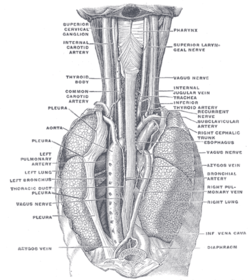

Base and diaphragmatic surface of heart. The position and relation of the esophagus in the cervical region and in the posterior mediastinum. Seen from behind.

The position and relation of the esophagus in the cervical region and in the posterior mediastinum. Seen from behind. Left atrium